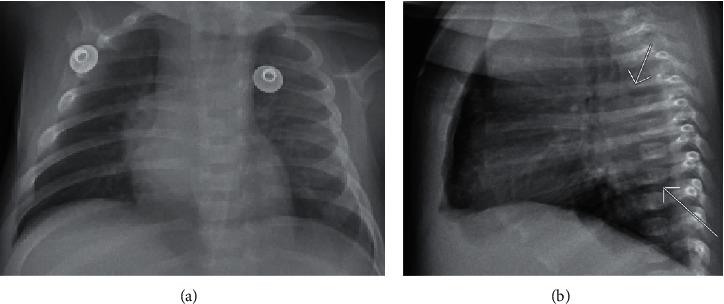

causes sepsis in neonates who are immunocompromised or exposed via nosocomial transmission. We report a case of sepsis in a previously healthy 5-week-old male originally treated for bacterial pneumonia per chest X-ray findings and 3 days of fevers. Regardless of appropriate antibiotics and an initial negative blood culture, he developed severe hypoglycemia, circulatory collapse with disseminated intravascular coagulopathy, and expired. A second blood culture taken following transfer to the intensive care unit resulted positive for postmortem. Review of the newborn screen and family history was otherwise normal. Subsequent postmortem autopsy showed multifocal bilateral pneumonia with necrotizing granulomatous and suppurative portions of lung tissue. Additionally, there was a prominent cavitary lesion 2.5 cm in the right lower lobe with branching and septate fungal hyphae. Stellate microabscesses with granulomas were present in the liver and spleen. These findings plus bacteremia are highly suggestive of an immunocompromised status. Review of the literature shows that its presence has been associated with chronic granulomatous disease. Therefore, in a persistently febrile infant not responding to antibiotics for common microbes causing community-acquired pneumonia, immunodeficiency workup should ensue in addition to respective testing for chronic granulomatous disease especially if culture-positive as it is strongly associated with neutrophil dysfunction.

在免疫功能低下或通过医院内传播而暴露的新生儿中引发败血症。我们报告一例败血症病例,患儿为一名此前健康的5周大男婴,最初根据胸部X光检查结果诊断为细菌性肺炎,并伴有3天发热。尽管使用了适当的抗生素且最初血培养结果为阴性,但他仍出现了严重低血糖、伴有弥散性血管内凝血的循环衰竭,并最终死亡。转至重症监护病房后采集的第二份血培养在尸检后结果呈阳性。新生儿筛查及家族史检查其他方面均正常。随后的尸检显示多灶性双侧肺炎,肺组织有坏死性肉芽肿和化脓部分。此外,右下叶有一个2.5厘米的明显空洞性病变,内有分支状和有隔膜的真菌菌丝。肝脏和脾脏有星状微脓肿伴肉芽肿。这些发现加上菌血症高度提示免疫功能低下状态。文献回顾表明其存在与慢性肉芽肿病有关。因此,对于一名持续发热且对引起社区获得性肺炎的常见微生物使用抗生素无反应的婴儿,除了进行慢性肉芽肿病的相关检测外,还应进行免疫缺陷检查,特别是如果培养呈阳性,因为这与中性粒细胞功能障碍密切相关。